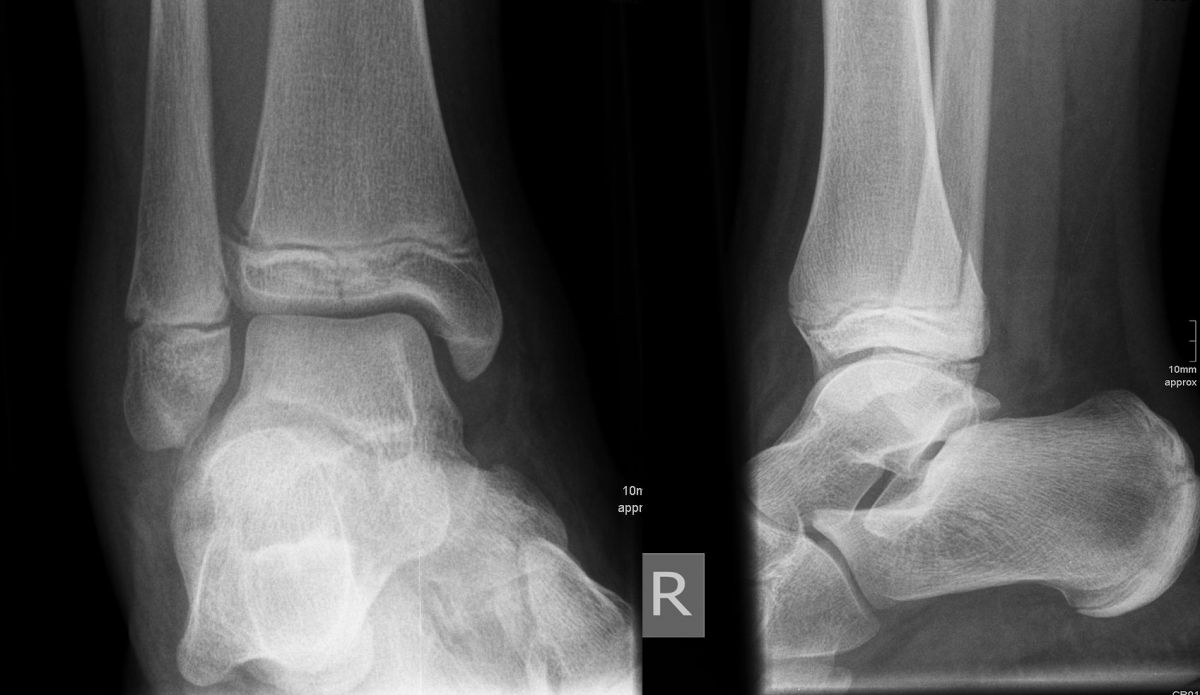

Mediale Malleolarfrakturen

Bei den medialen Malleolarfrakturen handelt es sich um Fugengelenkfrakturen bzw. Aitken II und III Verletzungen. Kennzeichnend ist, dass der Frakturverlauf die wachstumsaktive Zone zur Epiphyse hin durchkreuzt. Die Verletzung der wachstumsaktiven Zone macht diese Verletzungen besonders problematisch.

Fugengelenkfrakturen treten typischerweise vor dem 10. Lebensjahr auf, in einer Phase, in welcher die Wachstumsfugen noch weit offen sind. Dieser Frakturtyp betrifft fast ausschließlich den medialen Malleolus. Laterale Frakturen sind extrem selten, teilweise kommt es zu lateralen Bandverletzungen oder Fugenschaftfrakturen der distalen Fibula. Die Frakturlinie verläuft in einer Verlängerungslinie von der medialen Taluskante nach proximal. Häufig stellen sich Verletzungen des Innenknöchels im Röntgenbild schlechter dar, insbesondere wenn die Aufnahmen verdreht sind oder die Ebene der Fraktur bei geringer Dislokation verkippt zur Röntgenebene liegt. Besteht klinisch der geringste Hinweis auf eine Verletzung des Innenknöchels, muss aufgrund der Tragweite der Verletzung durch entsprechende Aufnahmen gegebenenfalls auch Schnittbildverfahren die Verletzung sicher diagnostiziert oder ausgeschlossen werden (Abb. 15).

Bei kindlichen Verletzungen des medialen Malleolus handelt es sich nach L. v. Laer um eine sogenannte Kadiläsion, d.h. eine Verletzung mit hohem Risiko eines schlechten Behandlungsergebnisses bei nicht korrekter Behandlung. Selbst bei optimaler Therapie ist das Risiko für spätere Wachstumsstörungen hoch, sodass diese Verletzungen nicht selten ein juristisches Nachspiel haben. Durch die Verletzung der wachstumsaktiven Zone kann es zu einem vorzeitigen Verschluss der Wachstumsfuge kommen, mit entsprechendem Fehlwachstum. Das Risiko eines vorzeitigen Verschlusses der Wachstumsfuge korreliert mit dem Ausmaß der Schädigung der wachstumsaktiven Zone. Ab dem 13. Lebensjahr wird das Risiko bei reduzierter Wachstumsaktivität zunehmend geringer.

Fugengelenkfrakturen können die Wachstumsfuge durchkreuzen (Abbildung 16a), ohne oder nur mit minimaler Beteiligung der Fuge sehr weit medial liegen (Abbildung 16b) oder durch die Fuge auslaufen (Abbildung 16c). Relevant für die Wachstumsprognose ist weniger die Form der Fraktur, sondern das Alter des Patienten zum Zeitpunkt des Traumas sowie das Ausmaß der Schädigung der Wachstumsfuge, wobei eine Korrelation mit dem Ausmaß der Dislokation besteht.